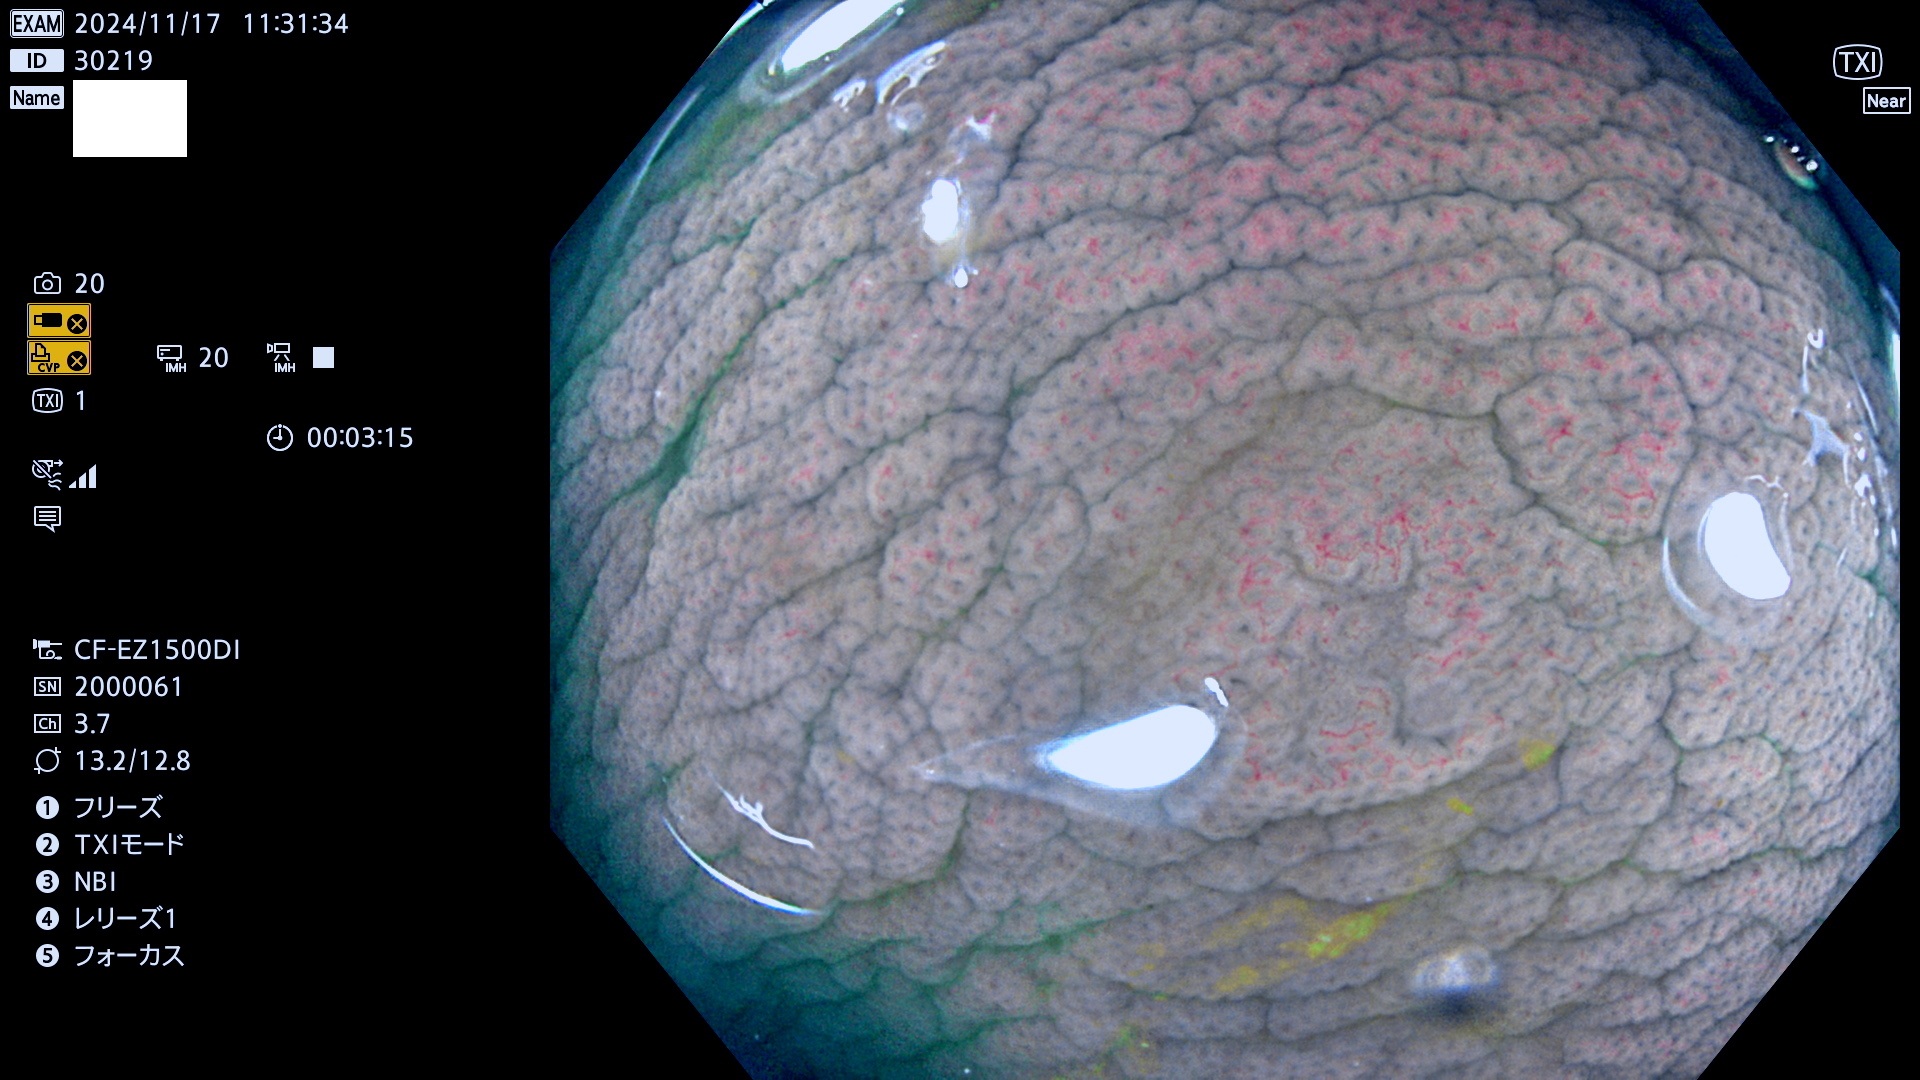

完全に平坦な物をUb、陥凹している物をUcと呼びます。最も発見が難しく危険な病変です。

専門的)Uc=De Novo癌? 内視鏡の解像度が低かった時代、このような説もありました。しかし今日の高精度内視鏡では良性の微小なUc型腺腫が日常的に見つかります。私見ですが「Ucこそが多段階発癌(Adenoma-Carcinoma Sequence)のMain Route」と考えます。

毎週の検査(木・金・土・日)に発見されたUb、Uc型・腺腫を、その週の日曜の夜にUPし1週間、提示します。

抽出の対象期間 2024年11月14日〜11月17日の4日間(48件の検査)7件 (7/48=14%)